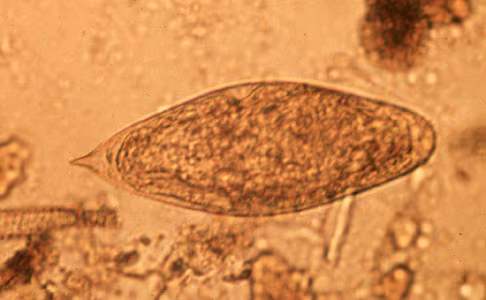

Schistosoma intercalatum eggs.